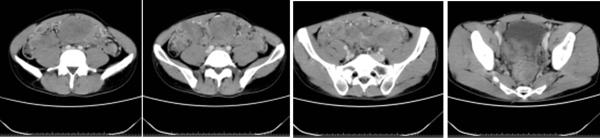

湖南日报·新湖南客户端 通讯员 刘兰 2020年3月,年仅32岁的小李第一次踏入湘雅常德医院肿瘤科门诊。 身材消瘦,165cm的身高体重仅50kg,下腹部可以摸到5*6cm大小的活动性肿块。这是小李留给湘雅常德...